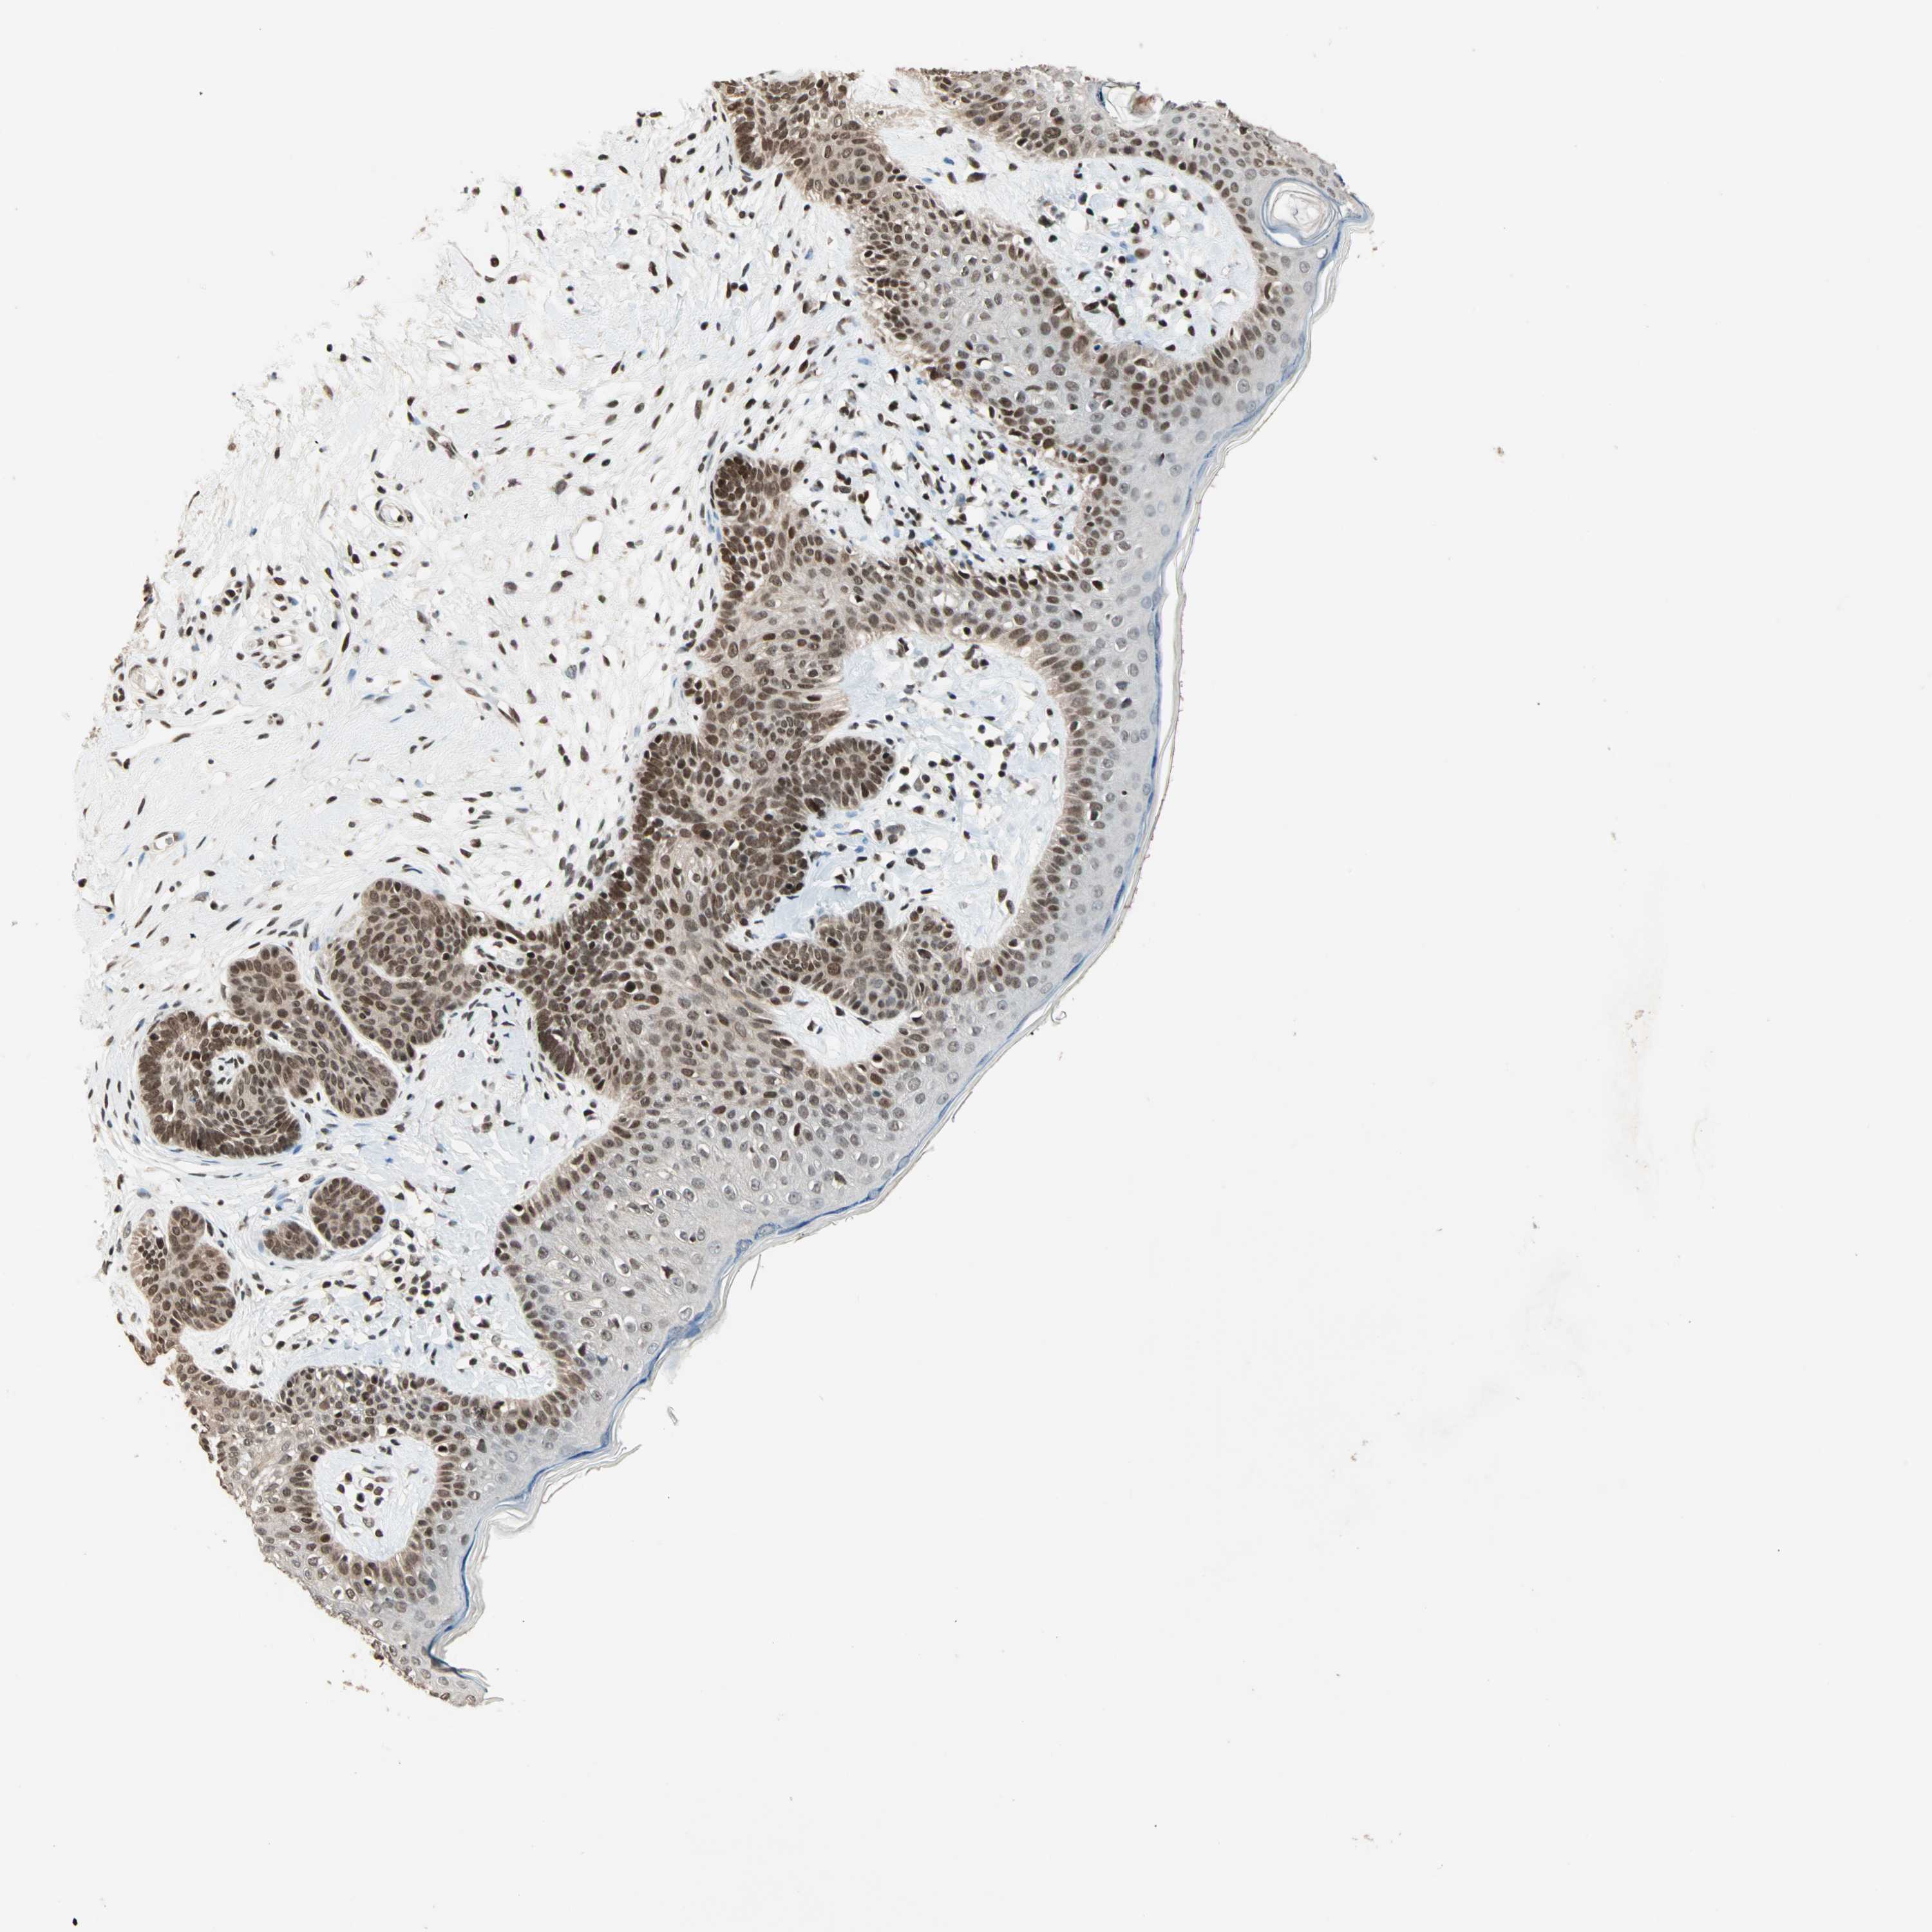

SKIN CANCER - Protein expressioni

A mouse-over function shows sample information and annotation data. Click on an image to view it in a full screen mode. Samples can be filtered based on level of antibody staining by selecting one or several of the following categories: high, medium, low and not detected. The assay and annotation is described here.

Antibody staining in the annotated cell types in the current human tissue is reported as not detected, low, medium, or high, based on conventional immunohistochemistry profiling in selected tissues. This score is based on the combination of the staining intensity and fraction of stained cells.

Each image is clickable and will lead to virtual microscopy that enables deeper exploration of all samples and also displays staining intensity scores, fraction scores and subcellular localization as well as patient and tissue information for each sample.

Antibody HPA006915

Staining

High

Intensity

Strong

Quantity

>75%

Location

Nuclear

Squamous cell carcinoma, NOS